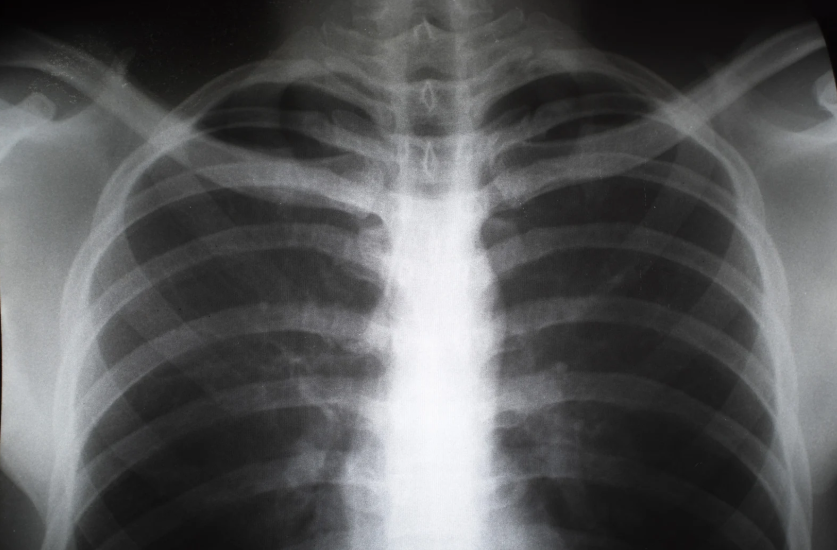

지역사회성 폐렴(Community-Acquired Pneumonia, CAP)은 병원이 아닌 지역사회에서 발생한 폐렴을 말합니다. 이는 폐렴의 가장 일반적인 형태로, 전 세계적으로 높은 발생률과 사망률을 보이며, 특히 고령자, 면역력이 약한 사람들, 만성질환을 가진 사람들에게 큰 위험을 초래할 수 있습니다. 지역사회성 폐렴은 다양한 원인균에 의해 발생할 수 있으며, 이에 대한 적절한 치료가 이루어지지 않으면 심각한 합병증을 초래할 수 있습니다.1. 지역사회성 폐렴의 원인지역사회성 폐렴의 원인은 주로 세균, 바이러스, 진균 등 다양한 병원체가 있습니다. 이를 구체적으로 살펴보면 다음과 같습니다.1) 세균성 원인폐렴구균(Streptococcus pneumoniae): 지역사회성 폐렴의 가장 흔한 원인균으로,..